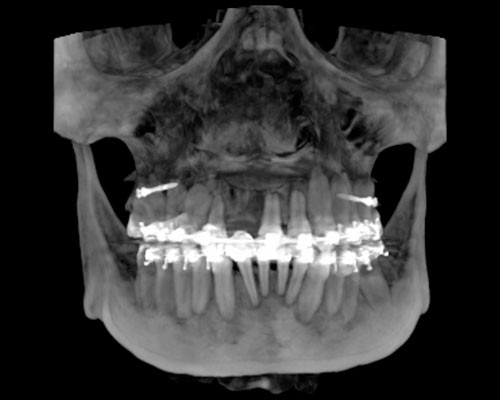

Precisión, eficiencia, calidad y oportunidad en todo el flujo de los tratamientos odontológicos

Exclusivo Sistema de Fotografía 3D disponible para todos nuestros clientes. IDM y Planmeca son pioneros en introducir este tipo de concepto en el Perú y consiste en la adquisición de una fotografía 3D sin necesidad de emitir radiación.